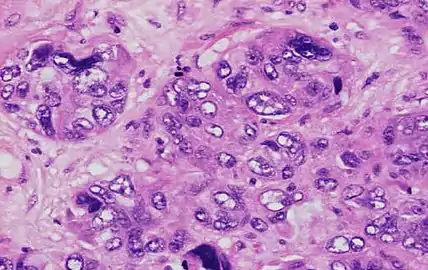

Invasive ductal carcinoma with moderate nuclear pleomorphism.

Invasive ductal carcinoma with marked nuclear pleomorphism.